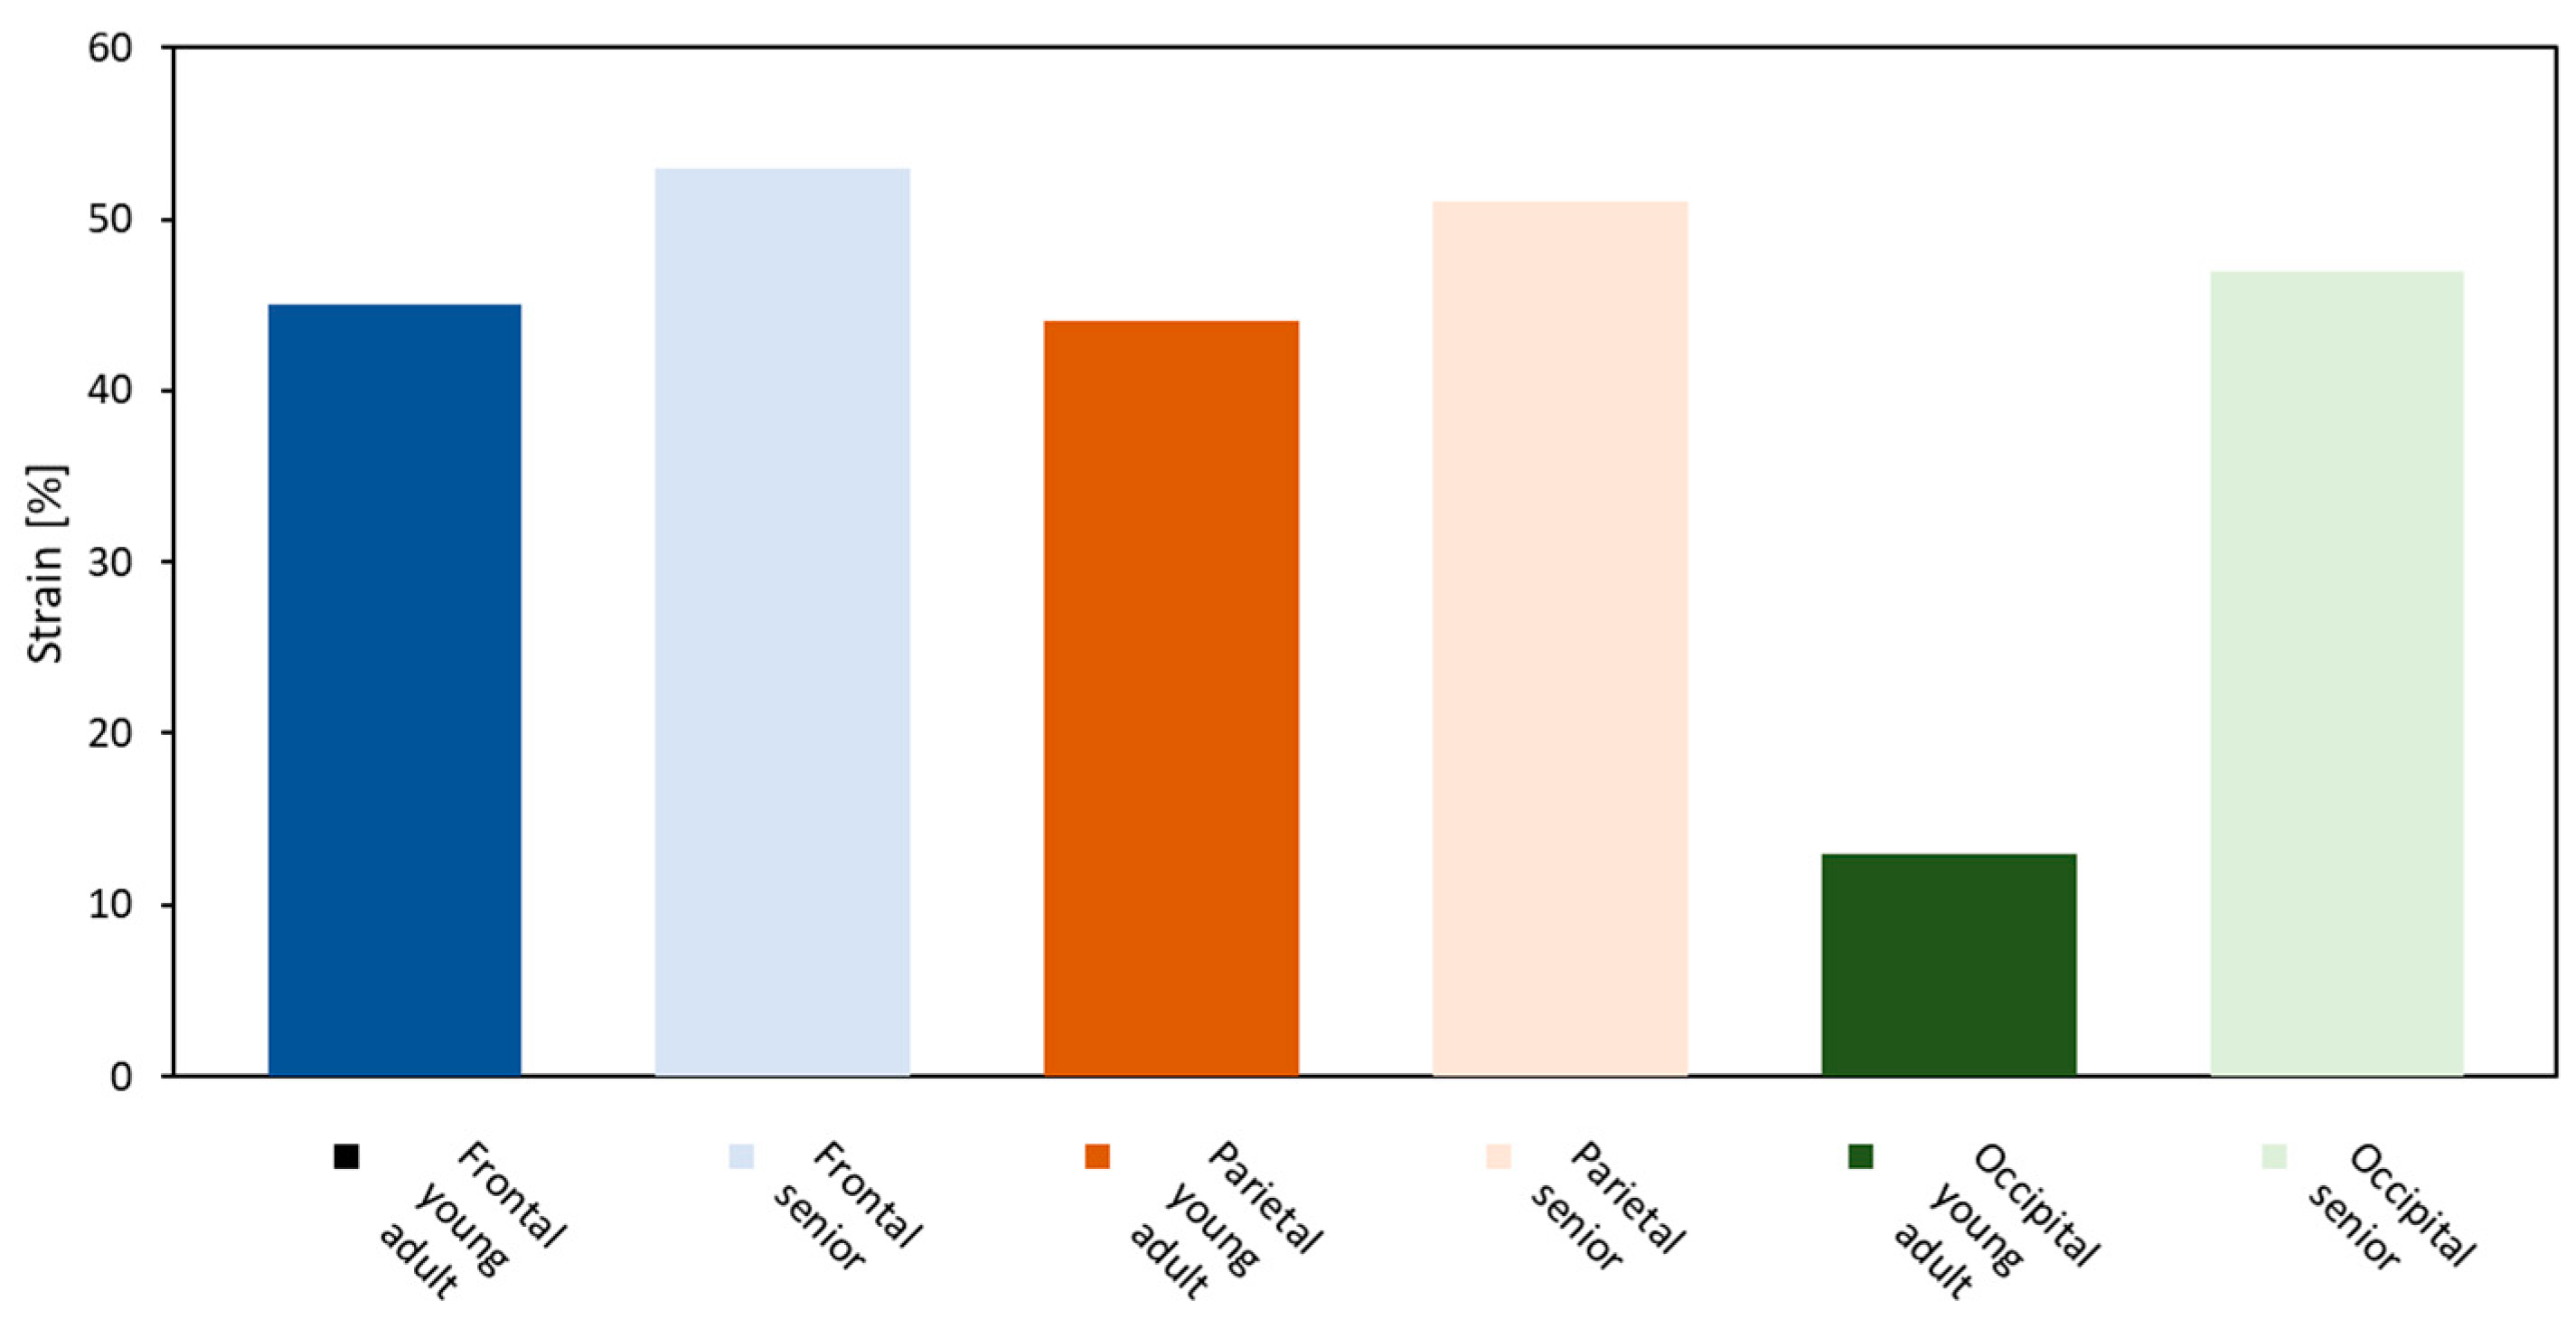

3. Results

Brain Physical Differences

| 28-Year-Old Model | 77-Year-Old Model | Effective Strain Criterion [-] | |

|---|---|---|---|

| Frontal veins |  |  |  |

| Parietal veins |  |  | |

| Occipital veins |  |  |